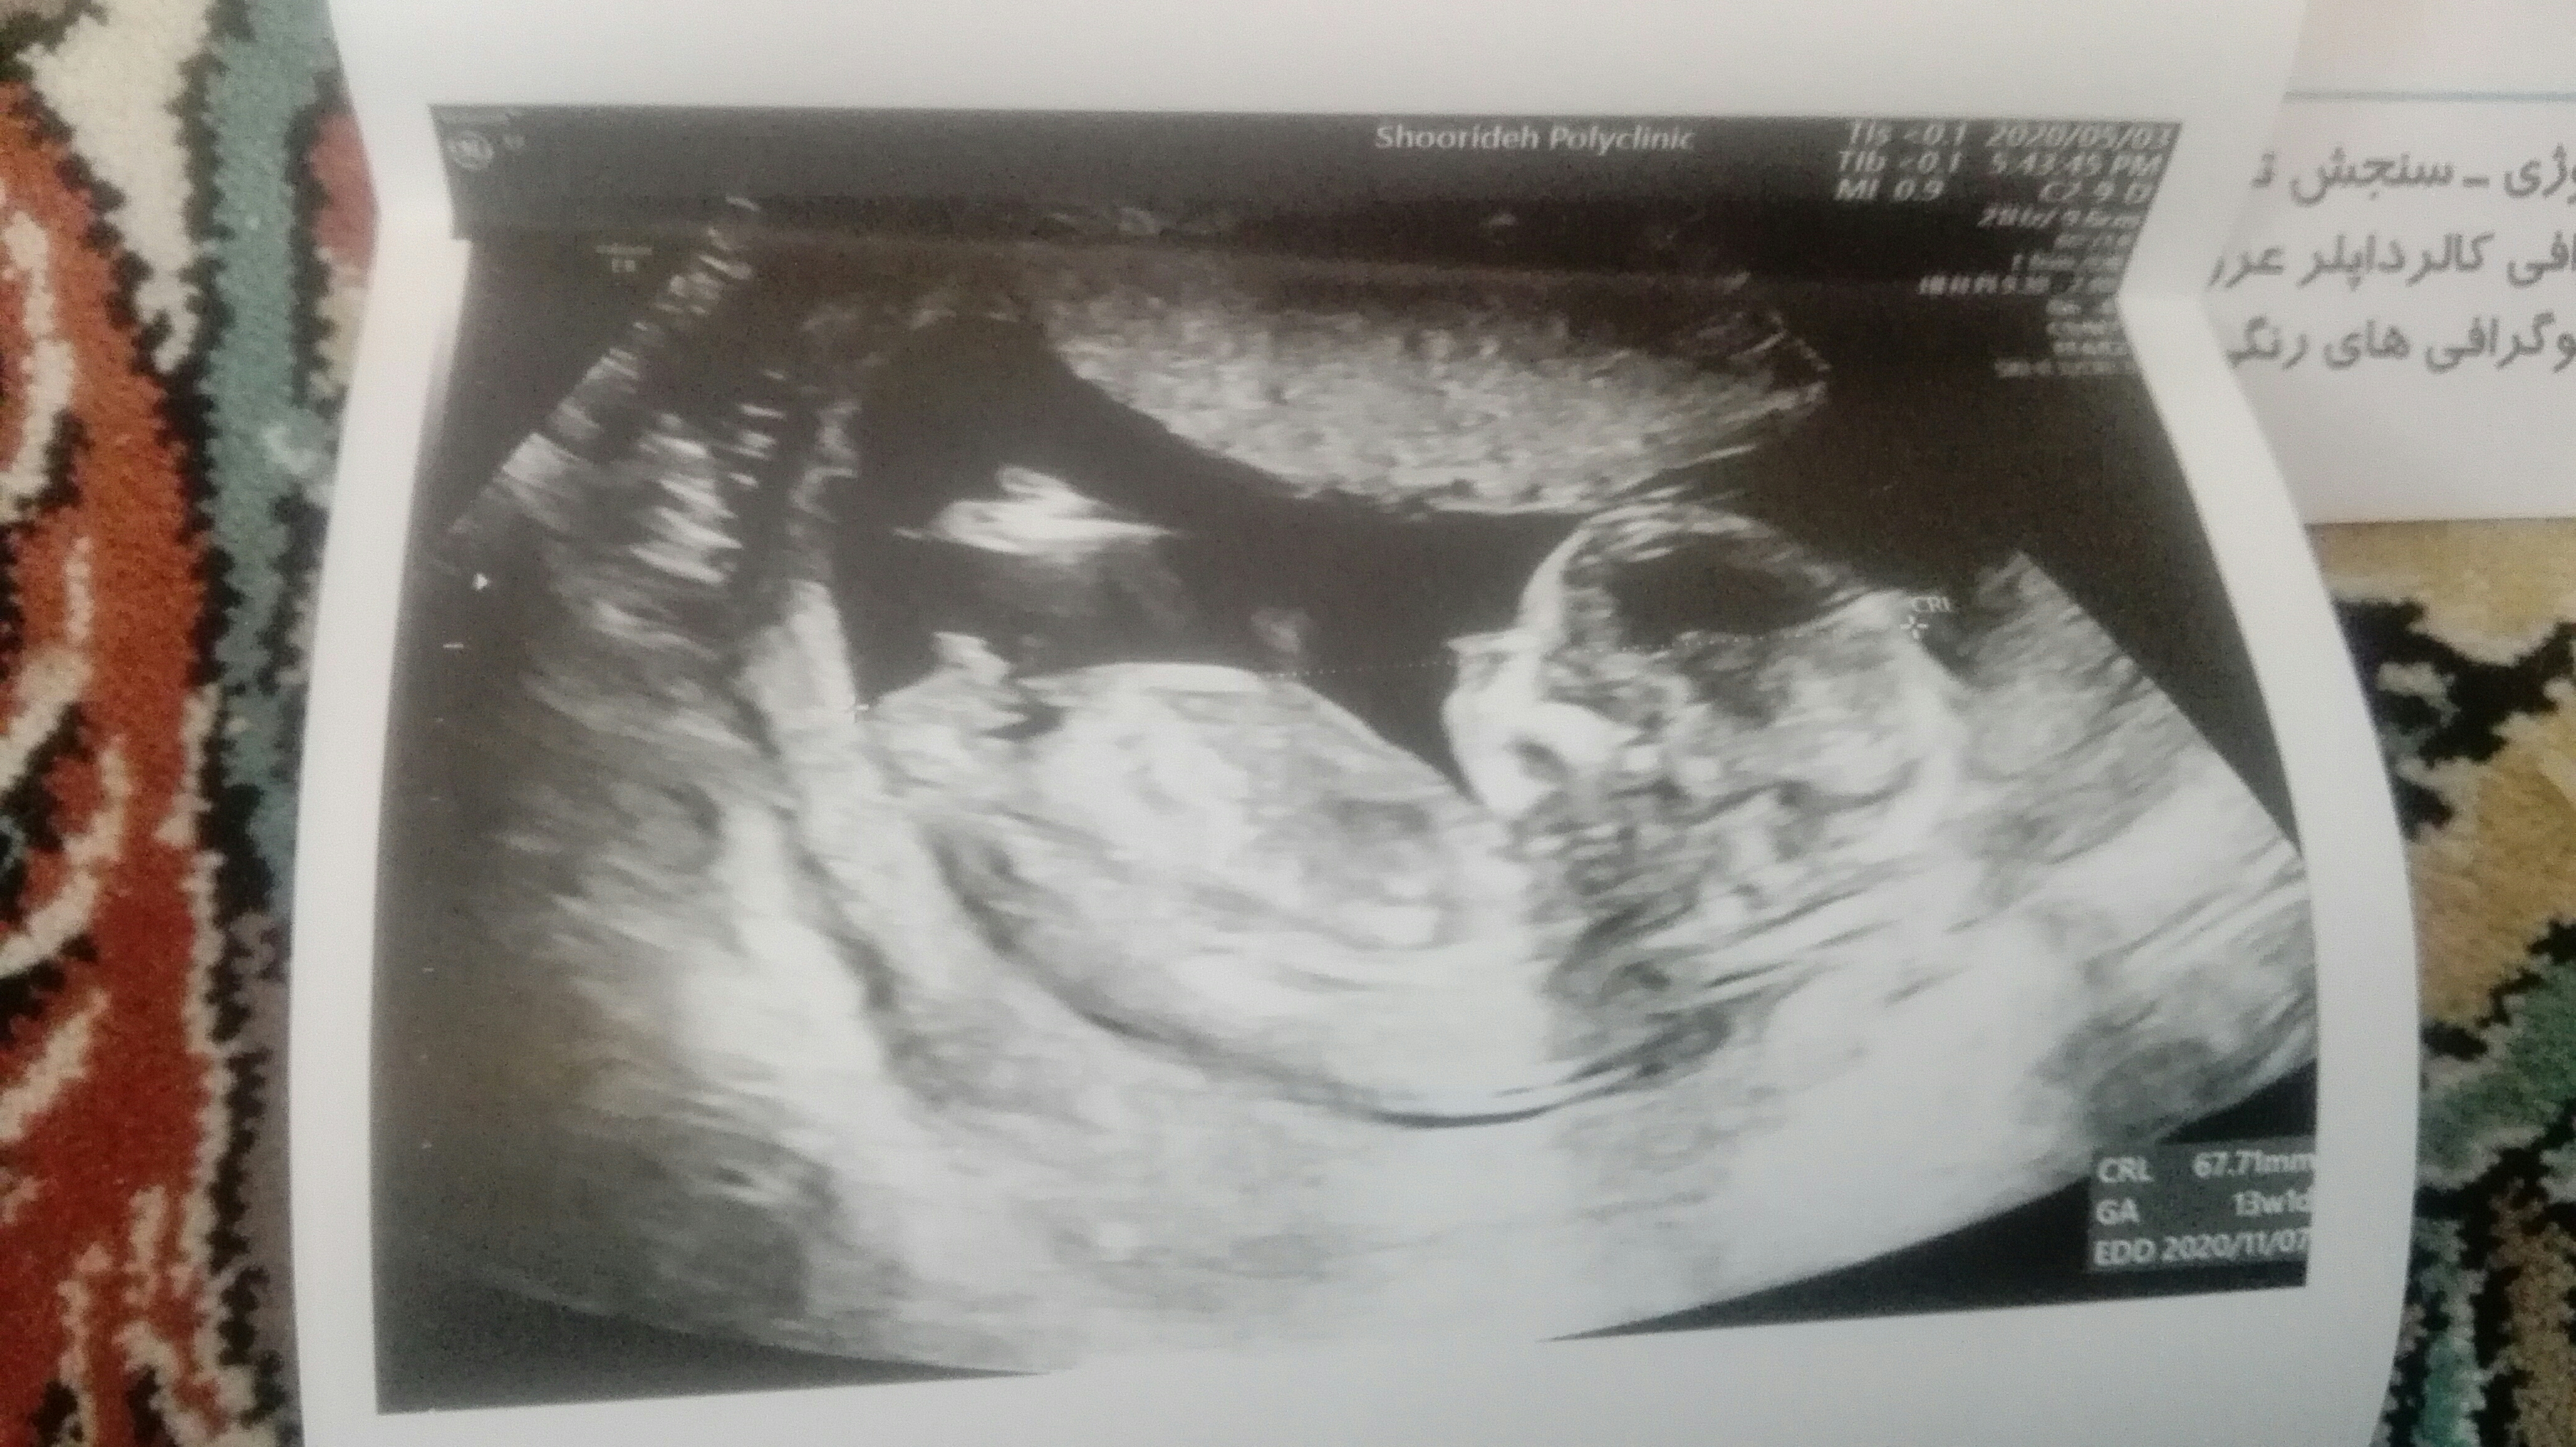

ب نظرم پسره...بهت چی گفتن؟

انگار یه چیزی بین پاهاش هست..البته به نظرم

من ی ساعت دیگه نوبت دارم پیش متخصص خودش سونو انجام میده خداکنه بگه جنسیتش چیه

گفتن ۶۰ در صد ممکنه پسر ولی استرس دارم زودی بفهمم